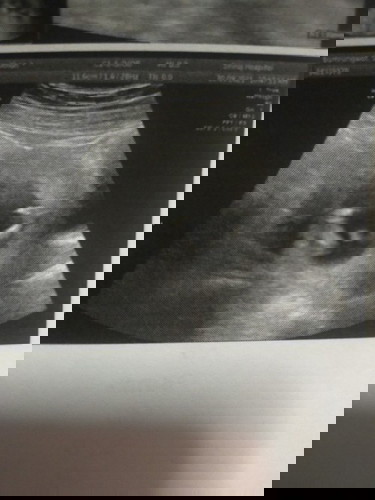

อันนี้ใช่จู๋น้องไหมคะ เห็นตั้งแต่รอบที่แล้ว แต่หมอบอกว่าตอนนี้ยังไม่ทราบเพศค่ะ

ตอนซาวด์อายุครรภ์กี่สัปดาห์แล้วคะ เราเคยซาวด์ตอน 12W เห็นเป็นลักษณะประมาณนี้เหมือนกันค่ะ แต่ลุงหมอบอกว่ายังไม่ฟันธงว่าเป็นผู้ชายนะคะ แบบนี้ทางการแพทย์เรียกว่าตุ่มเพศค่ะ สักพักอาจจะมีแฉกเกิดขึ้น ถ้ามีก็เท่ากับว่าน้องเป็นเพศหญิง ลุงหมอจะคอนเฟิร์มให้ตอน 16Wค่ะ สรุปเรารู้ผลเพศน้องจากการตรวจniftyตอน 14W แล้วลุงหมอก็ซาวด์คอนเฟิร์มให้ตอน 16W ยืนยันผลเป็นผู้หญิงตรงกันค่ะ